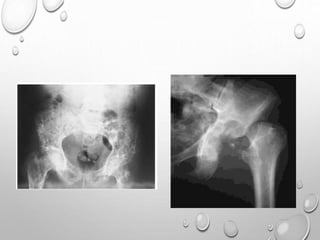

• 1. DYSPLASTIC OR SQUARE

ILIAC BONES

2. NARROW SACRO-SCIATIC

NOTCHES

3. FLAT BILATERAL

ACETABULAR ROOFS

4. SHORT BOTH FEMORAL

NECKS

5. CHAMPAGNE GLASS-

SHAPED PELVIC CAVITY